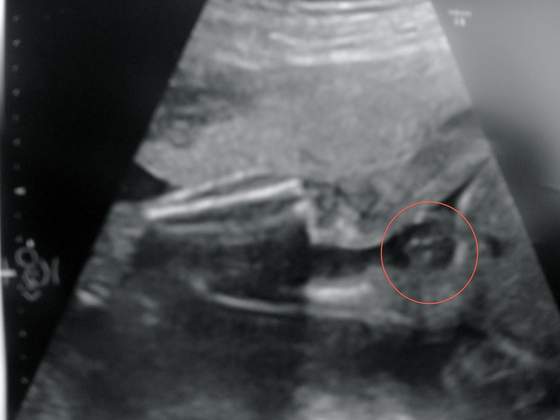

dziewczyny a tutaj wklejam dowód rzeczowy

jakby ktoś nie widział zaznaczone strzałeczką